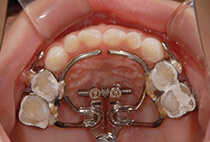

出っ歯を目立たずしっかり治したい。とのご希望、ビジネスシーンでも目立たないインビザラインを選択なさいました。30代男性の症例です。

治療計画は

抜歯した上顎も親知らずまできれいに並べたことで、上下ともに14本ずつ=非抜歯と同じ28本の歯列が完成しました。

治療から2年後も+ホワイトニングできれいな歯並びを保っています。

出っ歯が気になる

上顎前突、過蓋咬合

30代男性

3.5年

36回

唇側矯正、圧下用インプラントアンカー

矯正:1,270,500円+毎月調整量:6,050円

上顎2本抜歯して前歯を下げます。

奥歯のかみ合わせを治します。

インプラントアンカーを使用して前歯をしっかりコントロール、

過蓋咬合(かみ合わせの深さ)を改善しました。